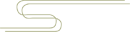

P,后方入路:首先建立,是主要的探查入路。 A,直接前方入路:主要的操作入路;多用途的;可用于诊断性关节镜检查,肩袖关节内面的清理及后方探查。 LA,低位前方入路:位于肩胛下肌腱上缘的正上方;该操作入路用于置入锚钉、关节囊紧缩,前方盂唇修复或关节囊缝合术的打结。 AS,前上方入路:位于肱二头肌滑车前方肩袖间隙的高位;用于从 11 点钟到 1 点钟位置上盂唇修复锚钉的置入;SLAP 修补打结;前方盂唇修复时理想的探查视野,或用于后方盂唇和关节囊的探查。 L,外侧入路:用于进入肩峰下间隙,肩袖修复。 7,后外侧入路(7 点钟位置):B 辅助入路用于后方盂唇锚钉的置入和修复。